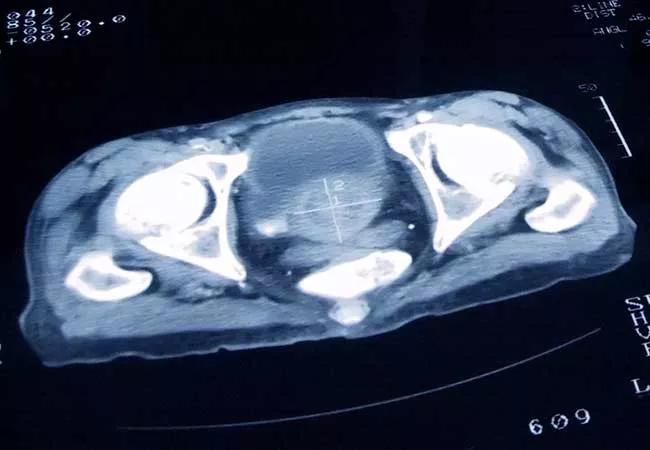

650×450-Prostate-Cancer